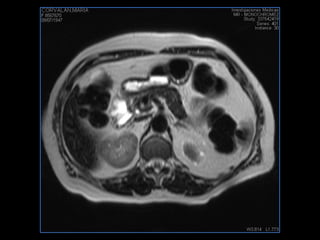

PROTOCOLO pancreas/ riñon AXIAL fat sat /AX in phase out phase AX T1 +SAG T2  COR T2, CON   GADOLINIO :  COR T1+AX T1(DIN) SAT: NO  FASE: RL THK: 4MM  COIL:  GAP: (FACTOR 1.4) 1MM FOV: 40 CM NEX:2 SINCRONIZACION RESPIRATORIA EN 3 O 4 CICLOS ALE